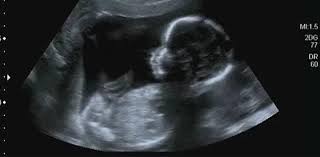

Hamileliğin ilk trimesterinin sonuna yaklaşıldığında, anne ve baba adaylarının en çok merak ettiği konulardan biri, minik yavrularının anne karnında neye benzediğidir. 12 haftalık bir bebek, bir avuç içini dolduracak kadar küçüktür ancak bu haftada gerçekleşen değişimler oldukça dikkat çekicidir. Bilimsel çalışmalar ve ultrason görüntüleri, bu dönemde fetüsün gelişimine dair çarpıcı bilgiler sunar.

Haftada bebek yaklaşık 5,5 cm uzunluğunda ve 14-20 gram ağırlığındadır. Bu, ortalama bir limon büyüklüğüne denk gelir. Bu dönemde en dikkat çekici özelliklerden biri, bebeğin insan görünümünü kazanmaya başlamasıdır.

- Yüz ve Organlar: Yüz hatları belirginleşmeye başlamıştır. Gözler ve kulaklar nihai yerlerine yaklaşır, burun ve çene yapısı daha net görülür. Ağız ve burun boşluğu gelişimi tamamlanmıştır. Hatta, bebeğin ultrason görüntülerinde gülümsemeye veya kaşlarını çatmasına benzer yüz ifadeleri sergilediği görülebilir.

- Dış Genital Organlar: Ultrason teknolojisindeki gelişmeler, bu haftadan itibaren dış genital organların oluşumunu gözlemlemeyi mümkün kılar. Her ne kadar kesin cinsiyet tespiti için biraz daha beklemek gerekse de, uzmanlar için bu yapıların gelişimi önemli ipuçları sunar.